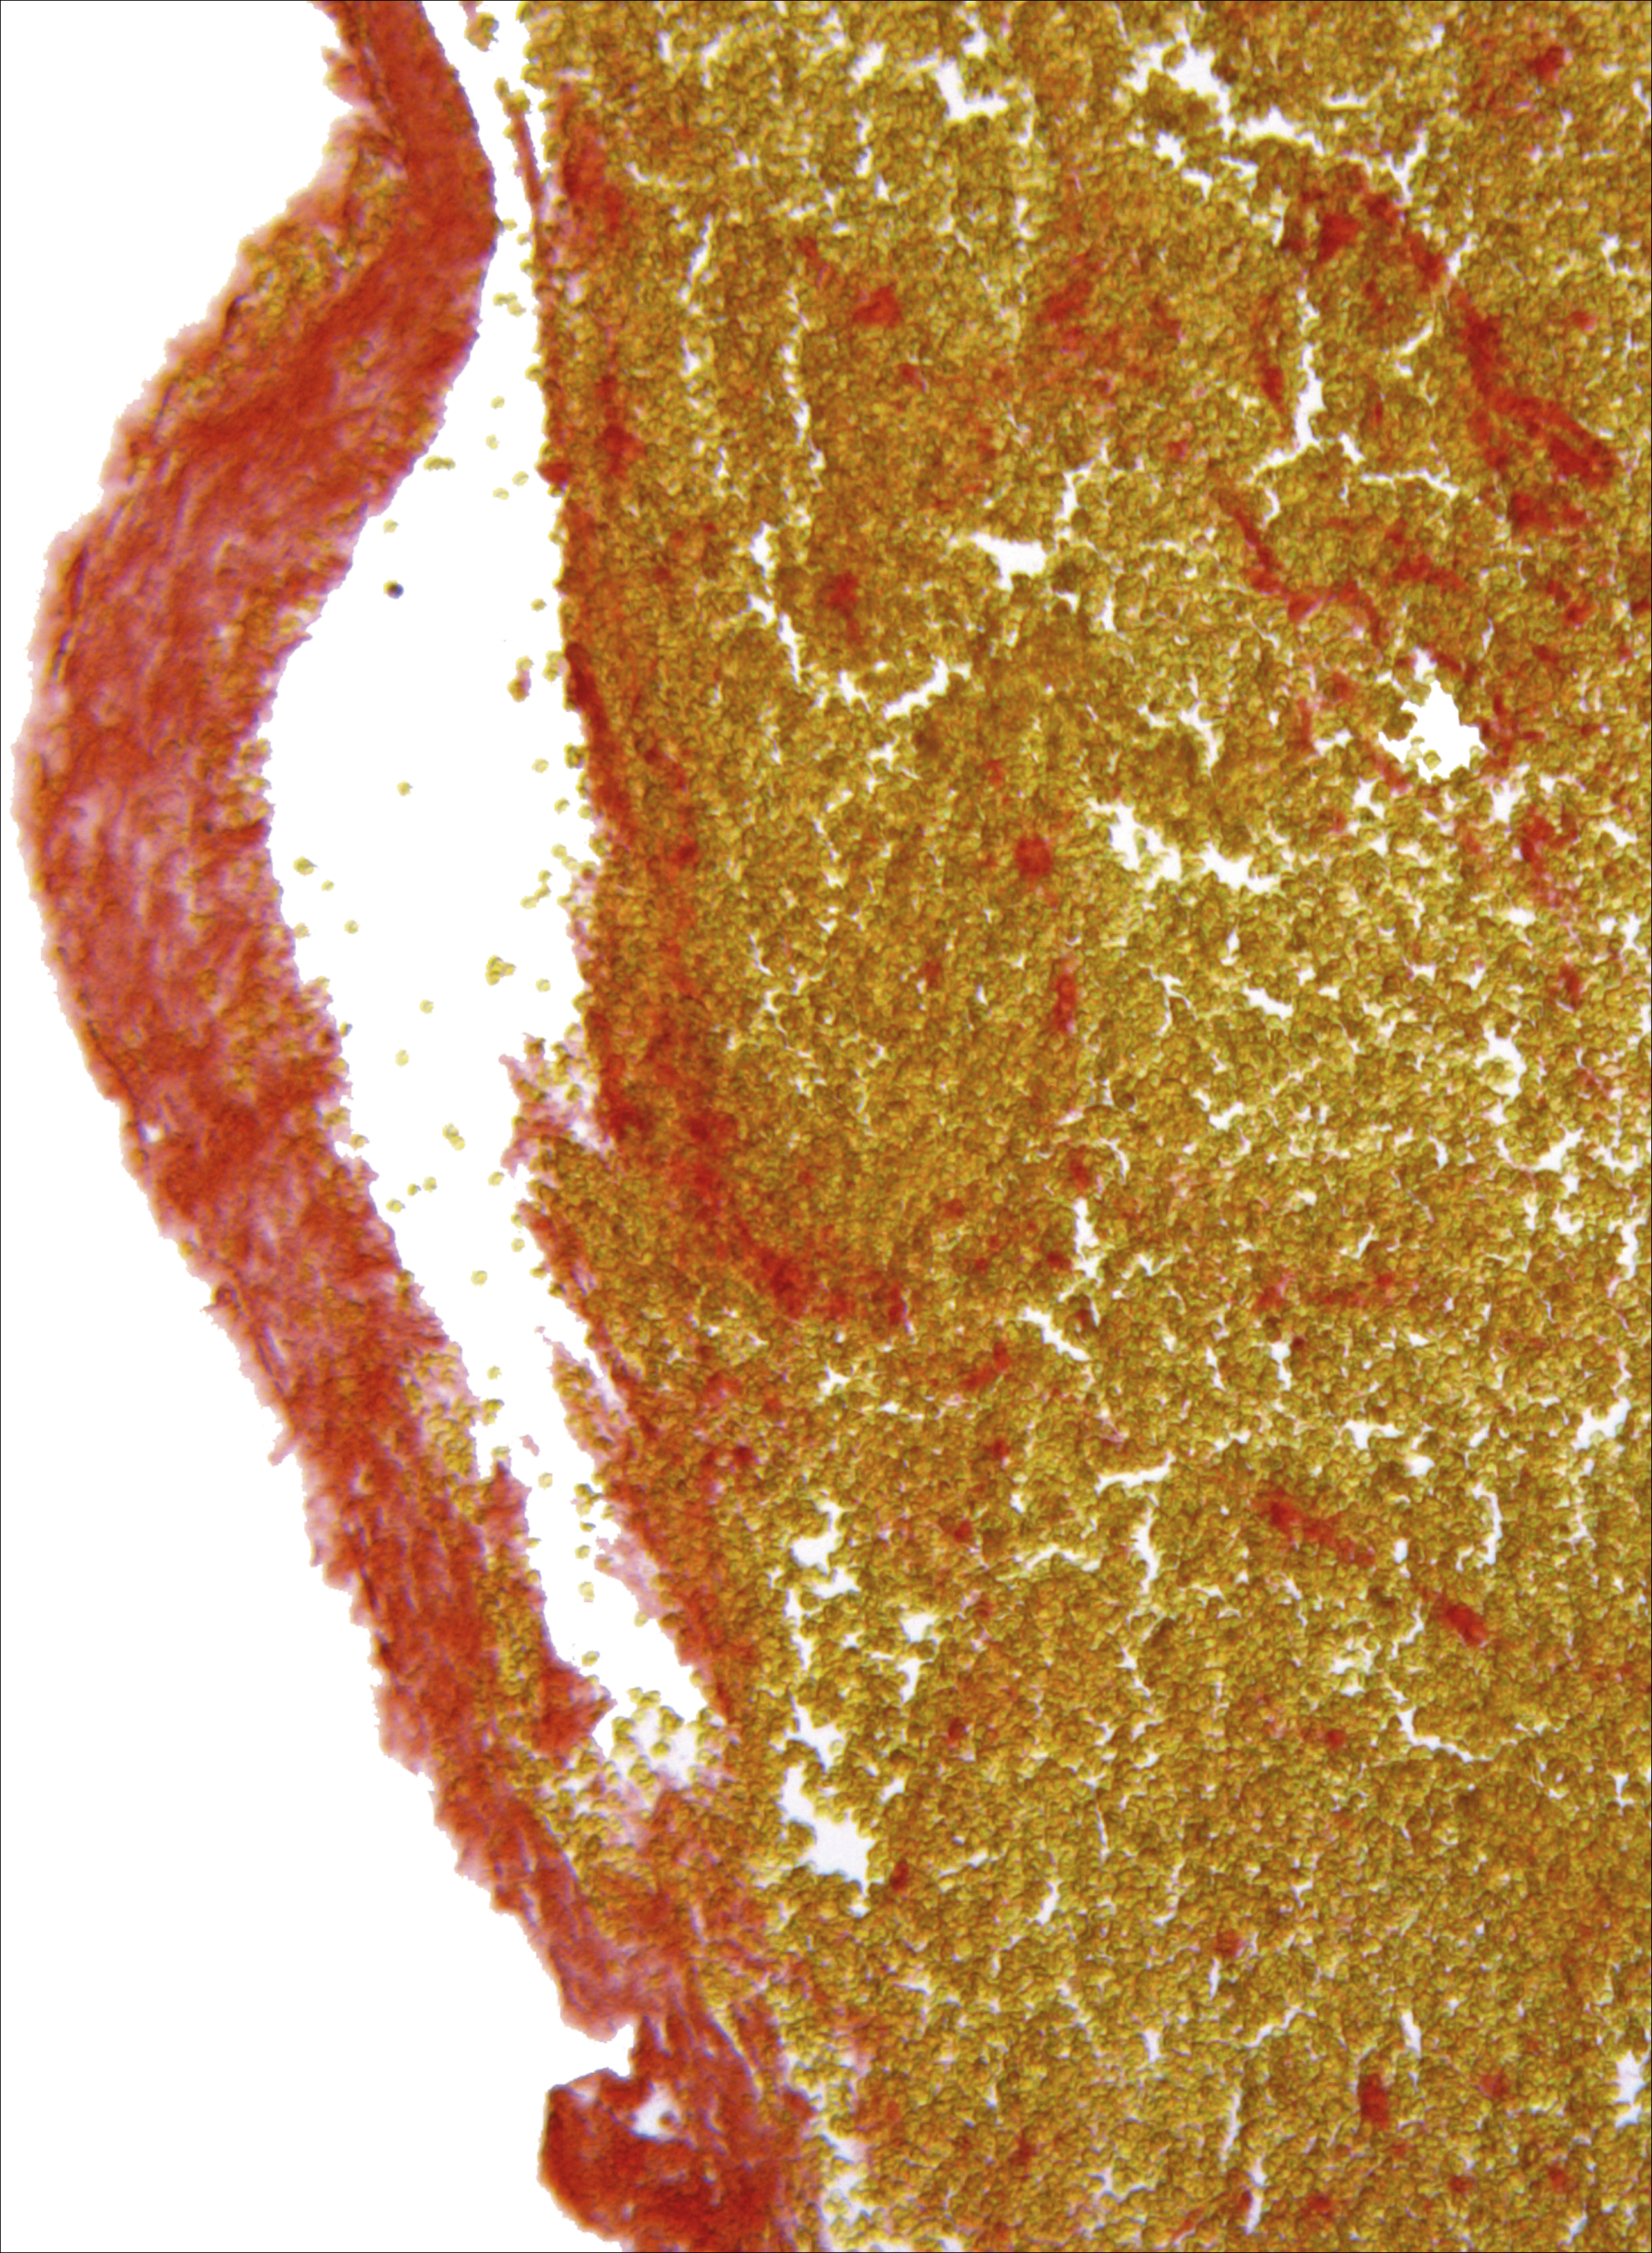

Histological analysis of occluding cerebral thrombi retrieved from stroke patients reveal variable composition patterns. A Martius Scarlet Blue staining of a red blood cell–rich thrombus is shown. Red areas indicate the presence of fibrin whereas red blood cells appear yellow. See the article by Denorme et al on page 2337.